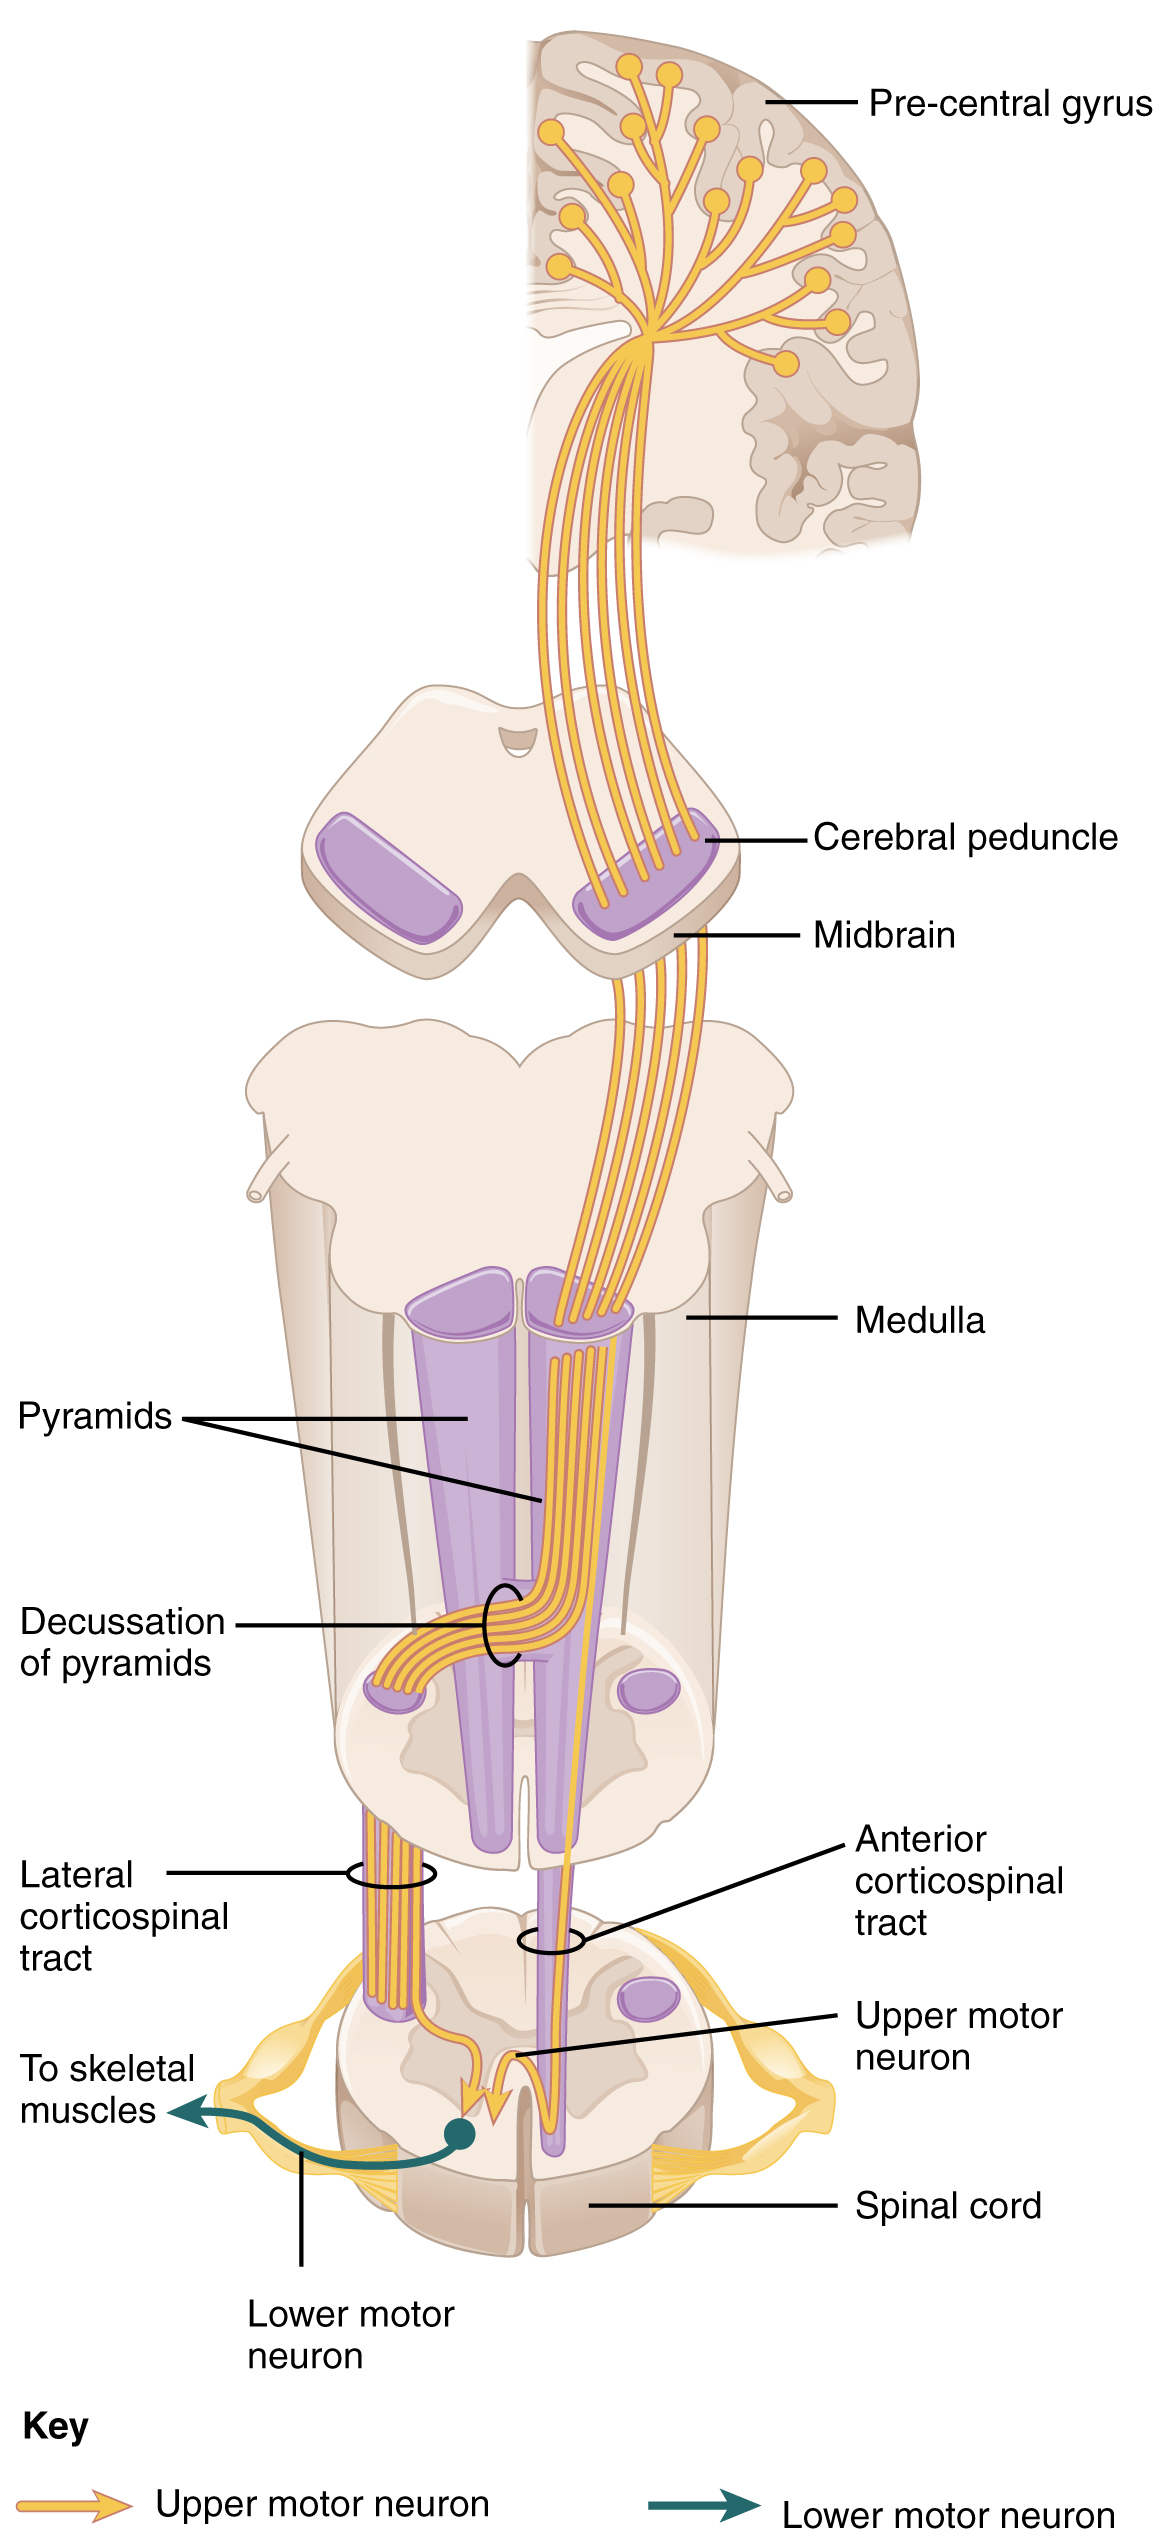

Brisa Alfaro, Pons Stroke/ Locked-In Syndrome Survivor Author, Speaker, Coach. - Corticospinal Tracts

Corticospinal Pathway.

Illustration of the motor neuron tract descending from primary motor cortex, via spinal cord, to skeletal muscle. - Extrapyrimidal Tracts